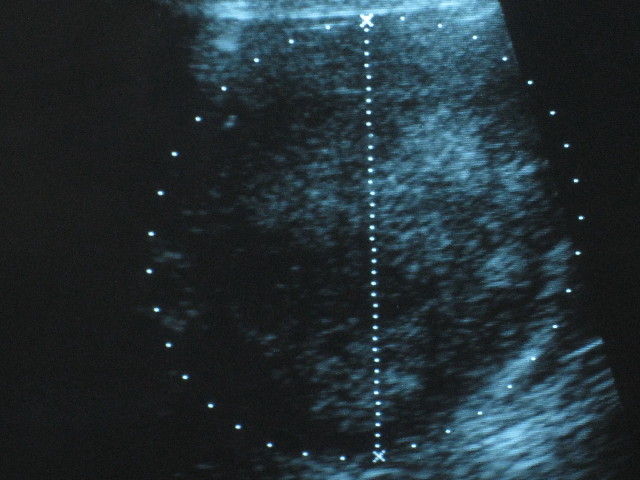

ついでに、エコーでバブちゃん(腎臓の腫瘍)も診てもらいました。

縦横ともに4.6cmくらいとのことで1月6日からはほとんど大きくなっていませんが

発見時の2011年9月26日は3×3.5cmくらいだったので、それと比べると4ケ月で直径が1cmちょっと大きくなってしまっています(;>_<;)

(測り方や、測る場所や、測る先生によっても違ってくるので一概にはいえませんが...)

ちなみに2011年12月5日は3.9×4.0cmくらいだったので、約2ケ月で0.6cmくらい大きくなってしまったことになります。